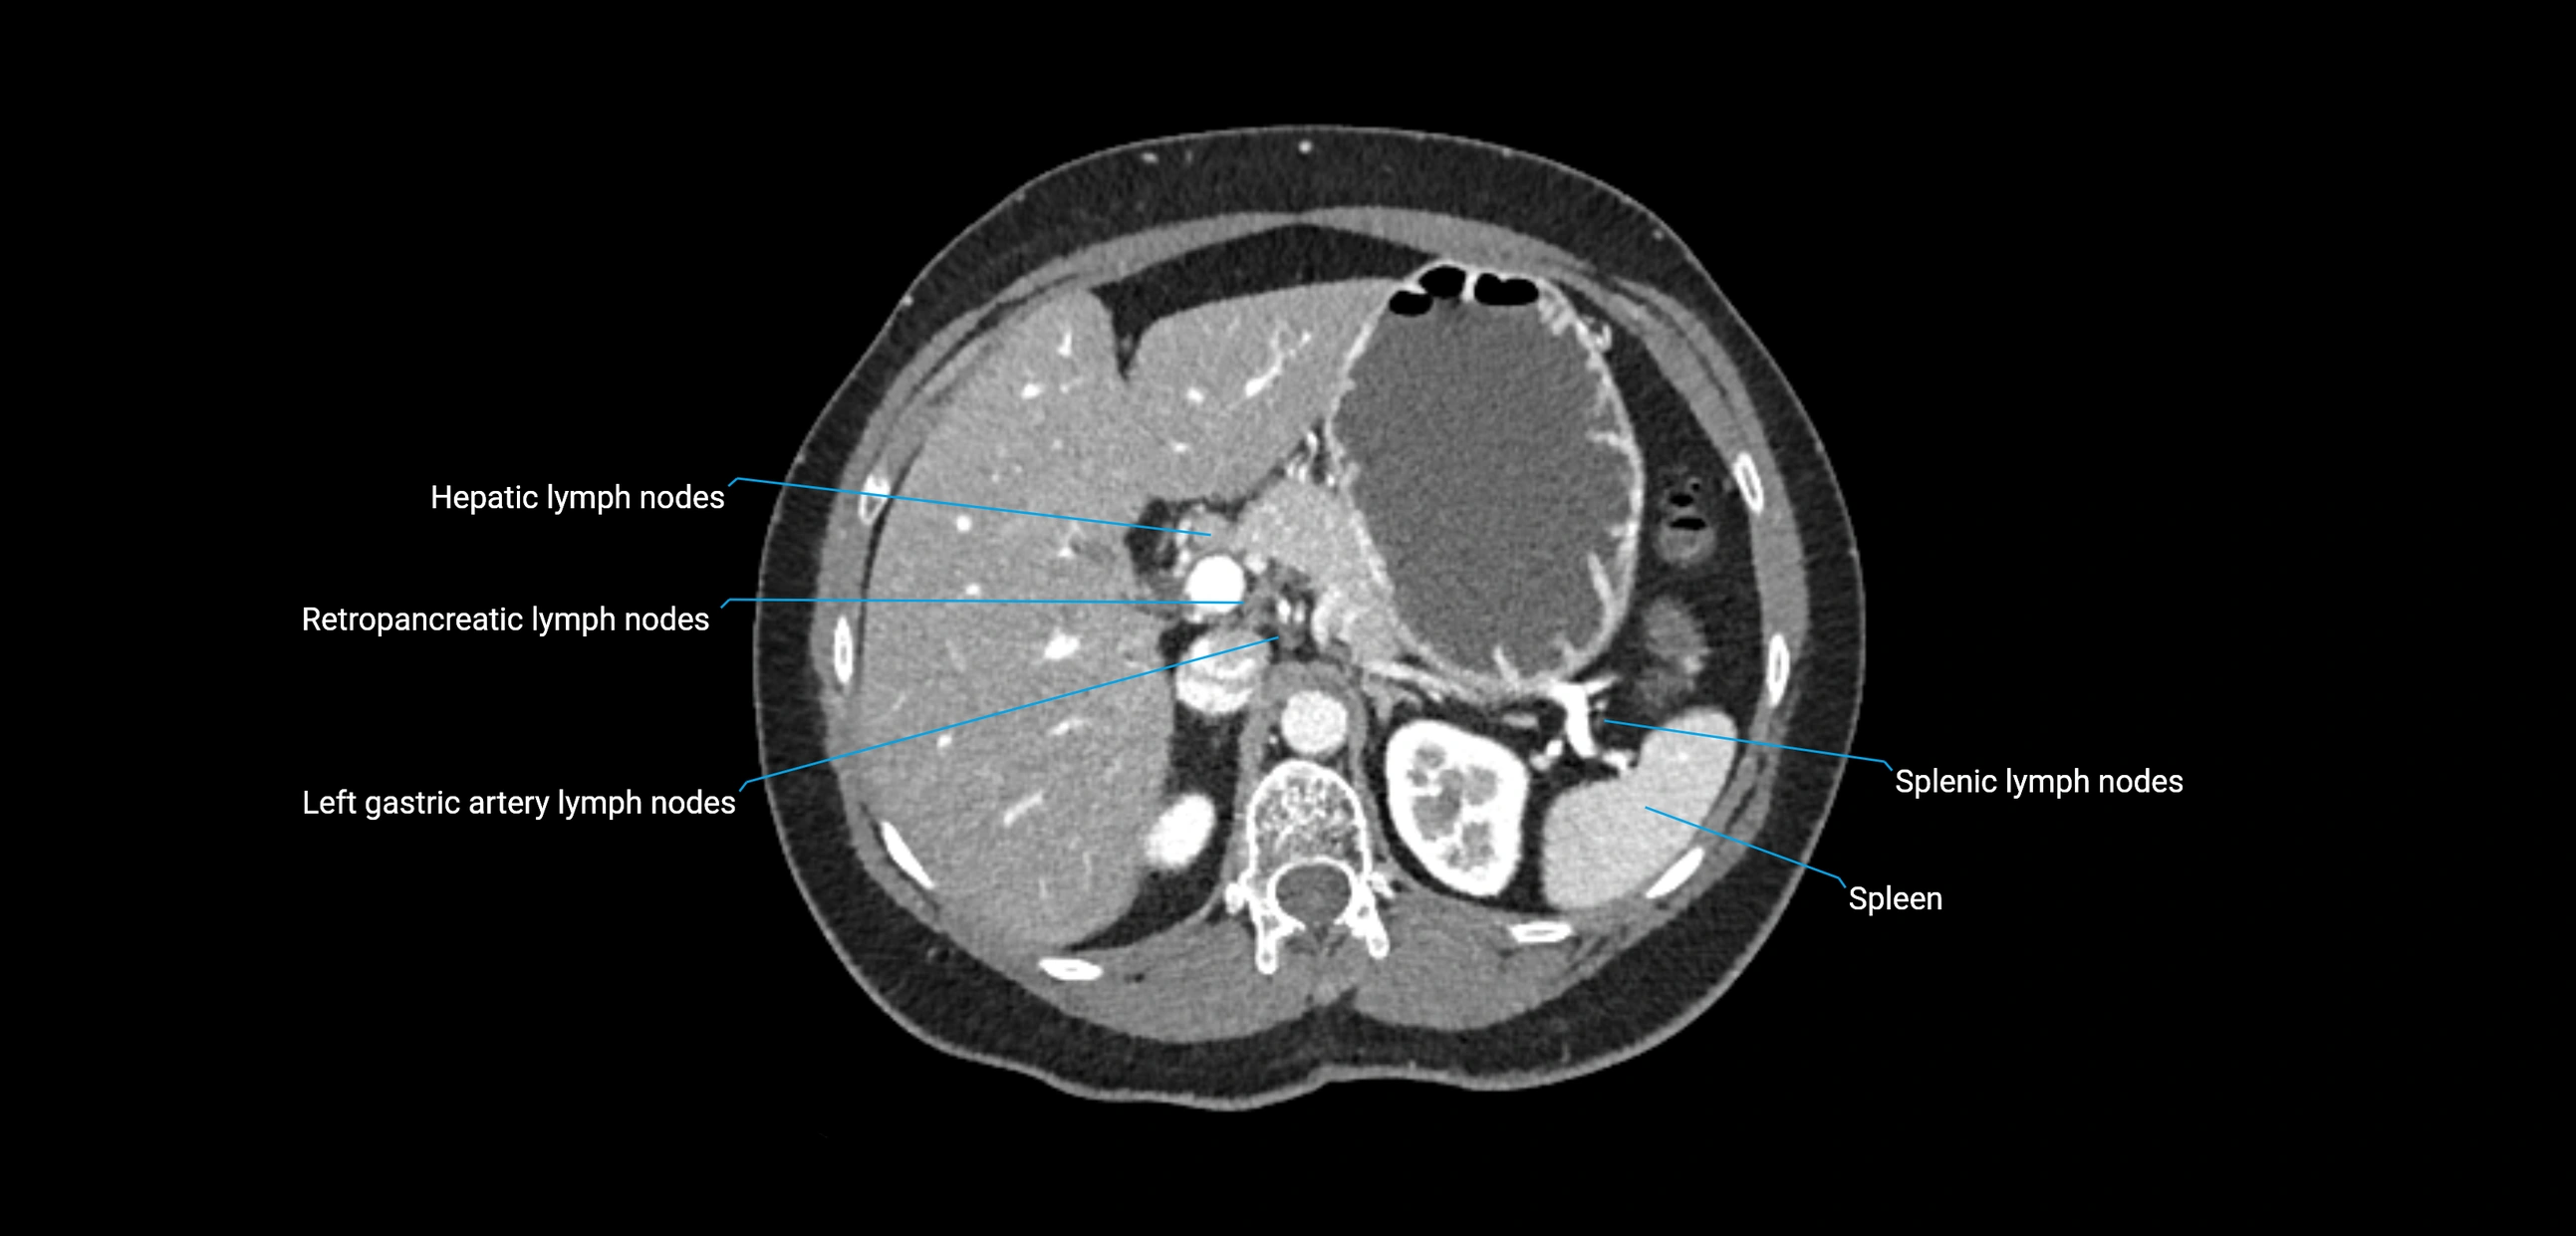

CT image

image